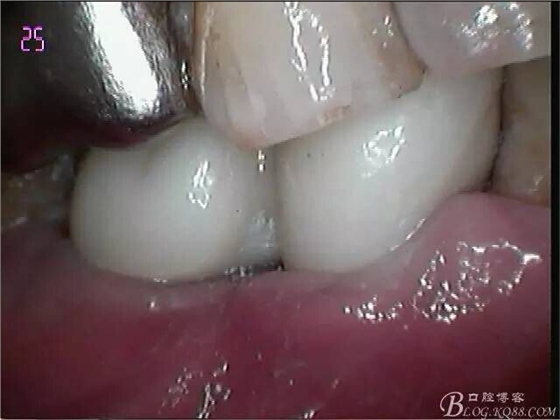

牙齦封閉良好,咬合,近中觸點穩(wěn)定